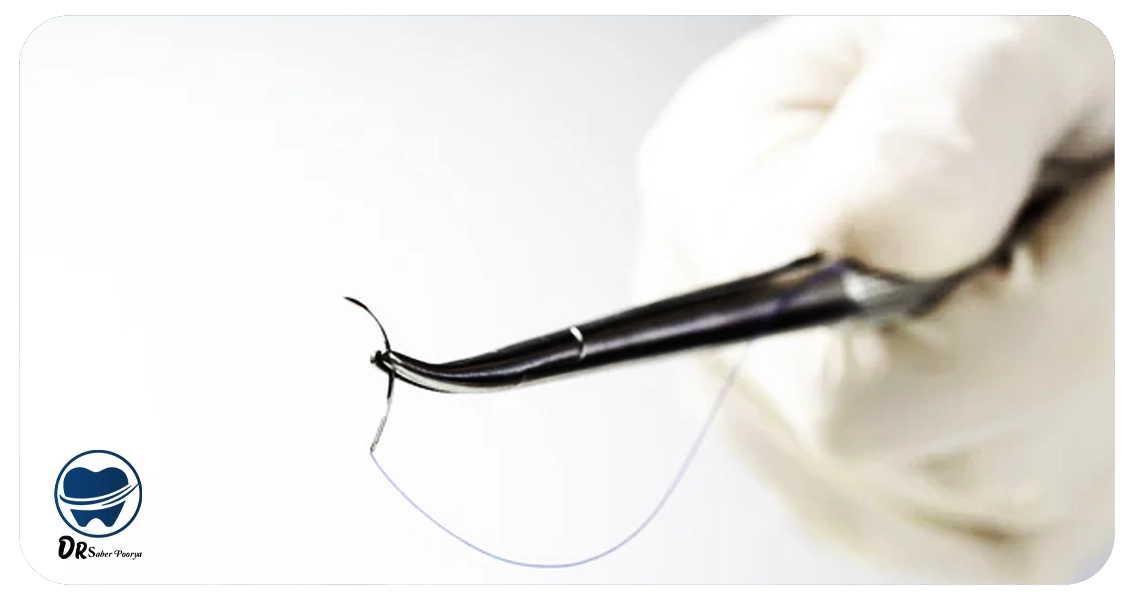

جراحان برای دسترسی به بافت استخوان و ایجاد برشهای دقیق در لثه، از بخیههای باکیفیت و مقاوم استفاده میکنند تا روند ترمیم بافت سریعتر انجام شود.

فرآیند برداشت بخیههای ایمپلنت معمولاً ساده و بدون دردسر انجام میشود. دندانپزشک با دقت یکی از گرههای نخ را جدا کرده و سپس بخیه را بهآرامی از بافت لثه خارج میکند.